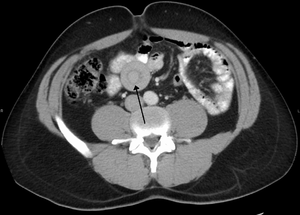

An intussusception is often suspected based on history and physical exam, including observation of Dance's sign. A digital rectal examination is particularly helpful in children, as part of the intussusceptum may be felt by the finger. A definite diagnosis often requires confirmation by diagnostic imaging modalities. Ultrasound is the imaging modality of choice for diagnosis and exclusion of intussusception, due to its high accuracy and lack of radiation. The appearance of target sign (also called "doughnut sign" on a sonograph, usually around 3 cm in diameter, confirms the diagnosis. The image seen on transverse sonography or computed tomography is that of a doughnut shape, created by the hyperechoic central core of bowel and mesentery surrounded by the hypoechoic outer edematous bowel.[7] In longitudinal imaging, intussusception resembles a sandwich.[7]